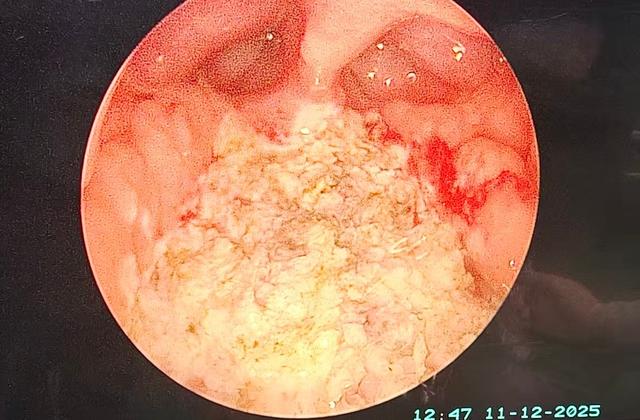

·治疗方式:目前,主流的手术是“鼻内镜下腺样体等离子消融术”,属于微创手术,创伤小、出血少、恢复快,绝大多数孩子当晚见效,术后正常饮食,几乎没有疼痛感觉,通常术后1-2天即可出院。对于合并扁桃体肥大、且扁桃体也频繁发炎或影响呼吸的孩子,医生可能会建议同时切除扁桃体。

术后:双侧后鼻孔开放,咽鼓管圆枕受压状态解除